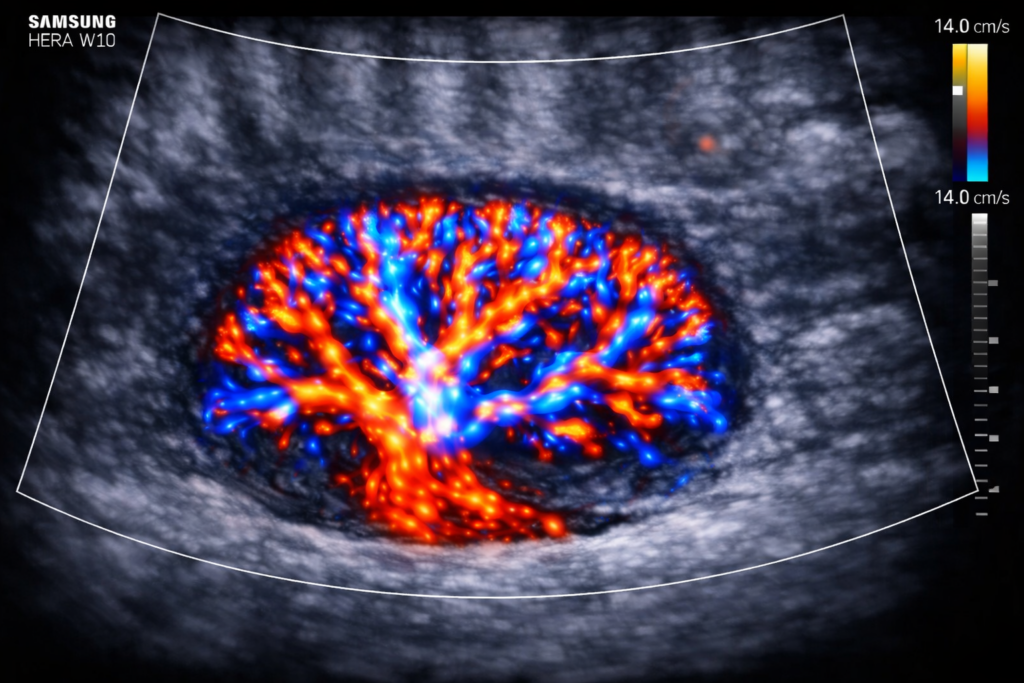

O exame Doppler vascular permite avaliar o fluxo sanguíneo em artérias e veias com análise técnica detalhada. Além disso, auxilia na identificação de obstruções, tromboses e outras alterações circulatórias. Dessa forma, contribui para um diagnóstico mais preciso e para a definição da melhor conduta clínica.

Realizamos o exame com equipamentos de alta definição, análise em tempo real e protocolo técnico direcionado ao território vascular estudado. Dessa forma, a avaliação ocorre com precisão e consistência diagnóstica.